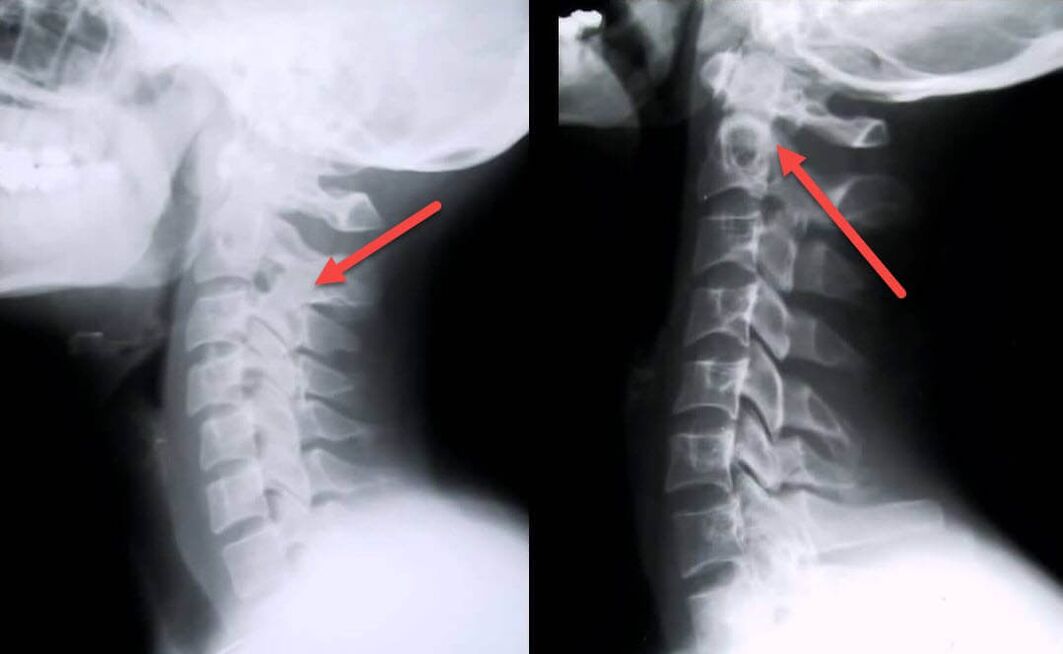

O procedemento diagnóstico máis informativo é a radiografía. As patoloxías de 1o grao corresponden á 1a ou 2a etapa radiolóxica. As imaxes resultantes visualizan sinais típicos de enfermidade.

| Etapas de raios X da osteocondrose cervical de 1º grao | Sinais característicos |

|---|---|

| Etapa 1 | Pequenos cambios na curvatura da columna vertebral na zona do pescozo, que afectan a un ou máis segmentos |

| Etapa 2 | Lixeiro engrosamento dos discos intervertebrais, deformación dos procesos uncinados, endereitamento da lordose, pequenos crecementos das estruturas óseas. |